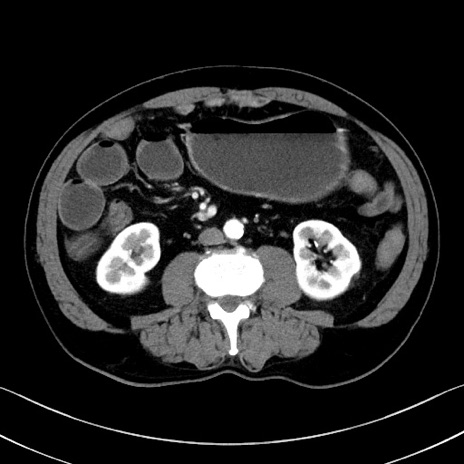

症例35(横断像)

冠状断像

【症例】70歳代 男性

【主訴】腹部膨満、嘔吐

【現病歴】昨日より腹部膨満感出現。本日増悪し、仙痛出現。嘔吐あり、受診。

【既往歴】糖尿病、胆摘後

【身体所見】BP 149/80mmHg、HR 74/min、BT 35.9℃、腹部:膨満、軟、圧痛なし。腸雑音減弱あり。上腹部正中切開瘢痕あり。

【データ】WBC 13500、CRP 1.72